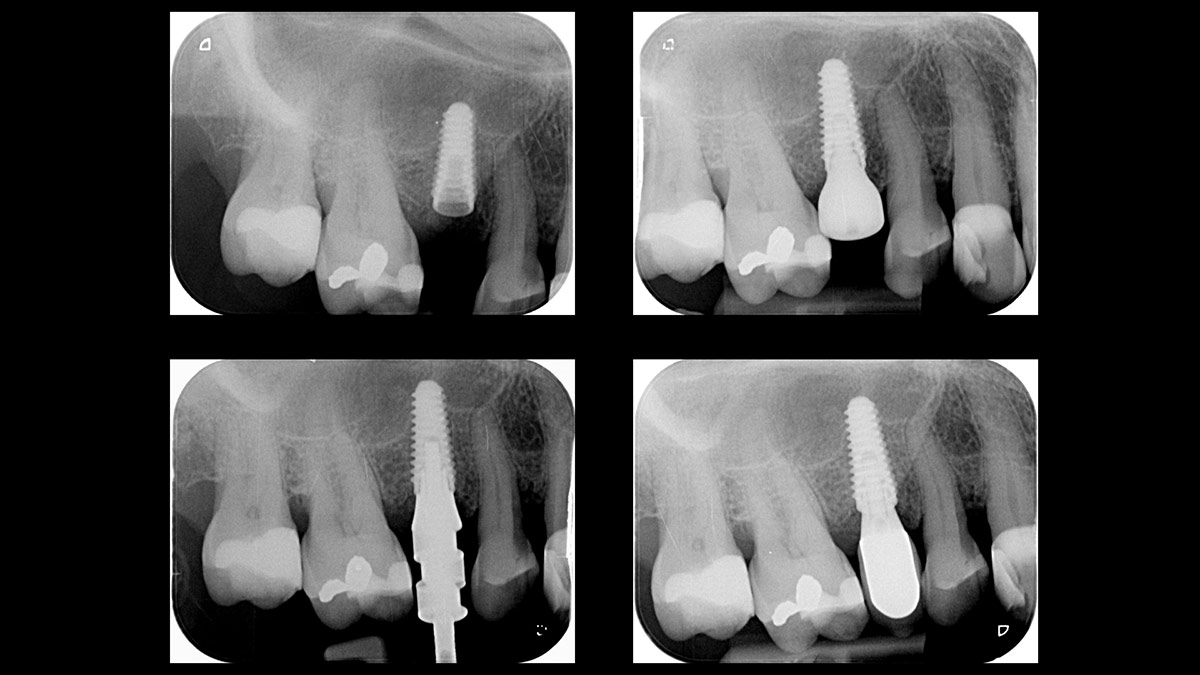

Immediate molars predictable? A case by @immediate_implantology